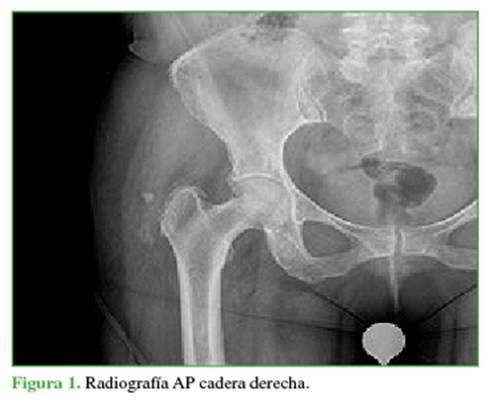

A la paciente se le realizan radiografías AP de pelvis y lateral de cadera derecha, las que informan fragmento óseo adyacente al trocánter mayor derecho, de 6 mm, ubicado en tejidos blandos de la cara lateral de la cadera (Figura 1). Dado que la paciente persiste con dolor intenso y limitación en la movilidad, ante la sospecha diagnóstica se prefiere realizar resonancia nuclear magnética por sobre tomografía axial computarizada.